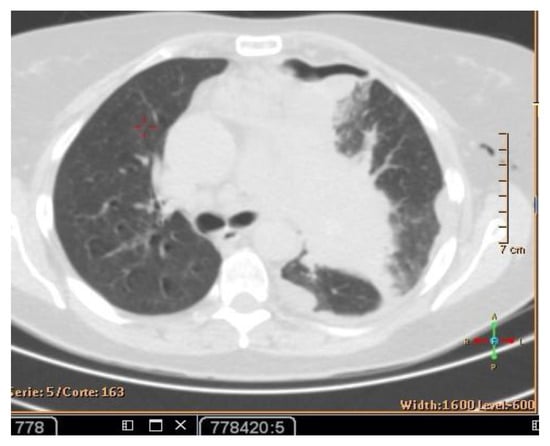

The patient’s history and physical examination as well as recent imaging evaluation should be well evaluated. Chest CT is the key imaging modality for evaluating lung tumor size and the location of lesions. Because of the complaint also of dysphagia, we conducted a CT scan of the chest, abdomen, and pelvis with means of contrast. A biopsy was taken as advised by [52]. The presence of small cell lung cancer, stage IVA (T4 N3 M1a) was confirmed. PET-CT and CT scans show images of a hypermetabolic left pulmonary hilar tumor (Figure 2).

Figure 2. CT scan (left) and Pet-CT (right) images of hypermetabolic left pulmonary hilar tumor from a female SCC patient.